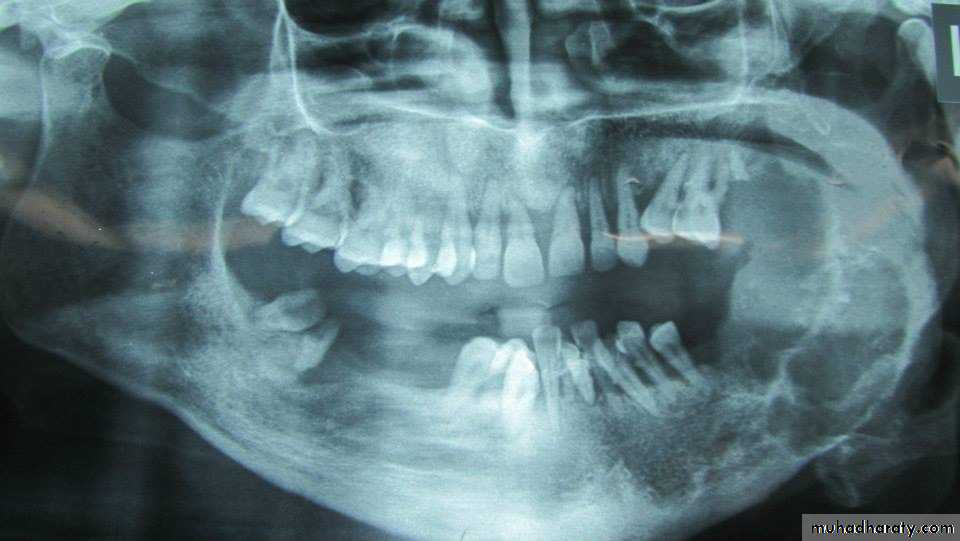

It is a tumor arising from embryonal cells of developing teeth. Although most forms of this tumor simulate other slow-growing benign tumors some can develop malignant tendencies.Patient may have few subjective symptoms during tumor growth. Enlargement of the tumor may expand the buccal, lingual or palatal bone plates. Tooth may be loosen and pressure symptoms may occur.

Raioraghical examination may demonstrate unlocular or multilocular types. Unilocular ameloblastomas may be confused with benign cysts. The tumors frequently absorbs the alveolus surrounding ,the roots of teeth and may absorb root ends.

Ameloblastoma grow by extension into adjacent tissues and may perforate the investing bone. A biopsy should precede treatment since

these tumors frequently present with individual characteristics.